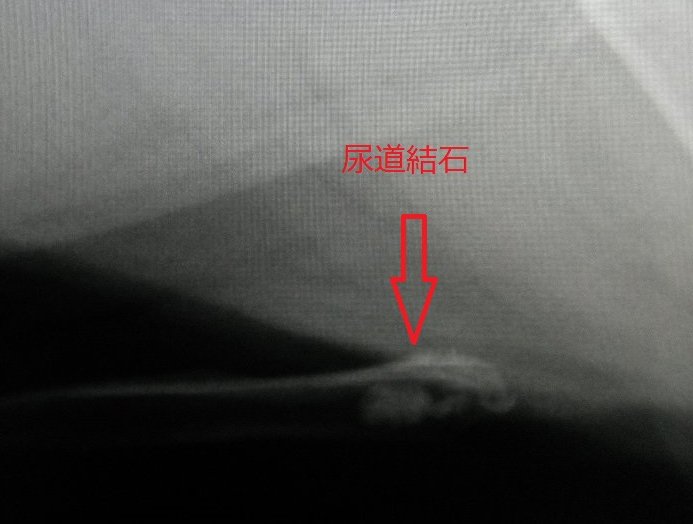

今回の症例は14歳の小型犬。

尿道結石との事で近隣の先生より外科紹介で来院されました。

数日間、血尿・頻尿がつづいていました。

詰まりの程度はすでにきつく、無麻酔にて尿道閉塞解除を試みるも結石が膀胱内に戻らず、

麻酔下にて実施も戻りませんでした。

何度やっても戻らないので外科処置に移行しました。

外科的に尿道切開を実施し、結石除去、同時に膀胱内にある結石も除去し、尿道、膀胱縫合を行い手術を終了しました。

(写真は尿道切開の写真です)